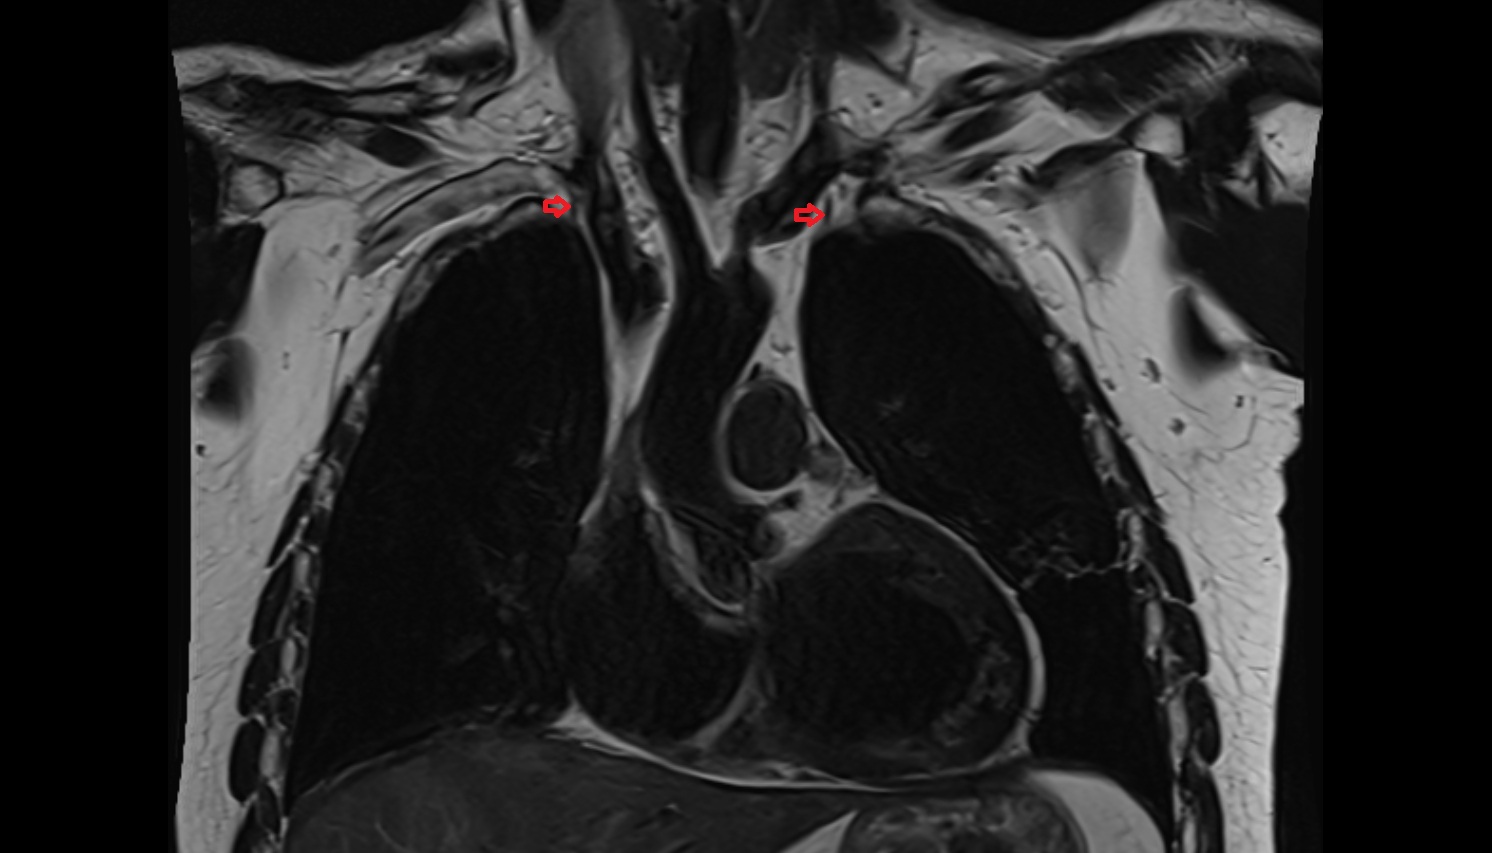

- Thymus